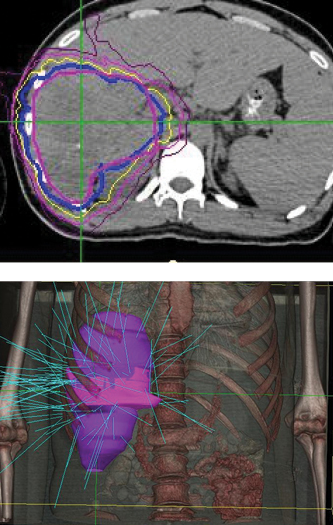

Phase 1 treatment covered the right lower lobe and hilar nodes, divided into two targets. The prescription was 48 Gy, delivered in four 12 Gy fractions for each of the two targets. Bilirubin fluctuations were noted during the course of therapy, but gradually returned to normal after treatment. One month after radiotherapy, a CT scan showed tumor shrinkage. The left lobe had sufficiently enlarged in compensation, so the second stage of treatment was initiated.

Phase 2 treatment covered the right upper lobe, divided into two targets: The prescription was 39 Gy, delivered in three 13 Gy fractions for each of the two targets.

“The patient lived more than two years with good quality of life after initial diagnosis, when life expectancy would have been one month without CyberKnife treatment.”